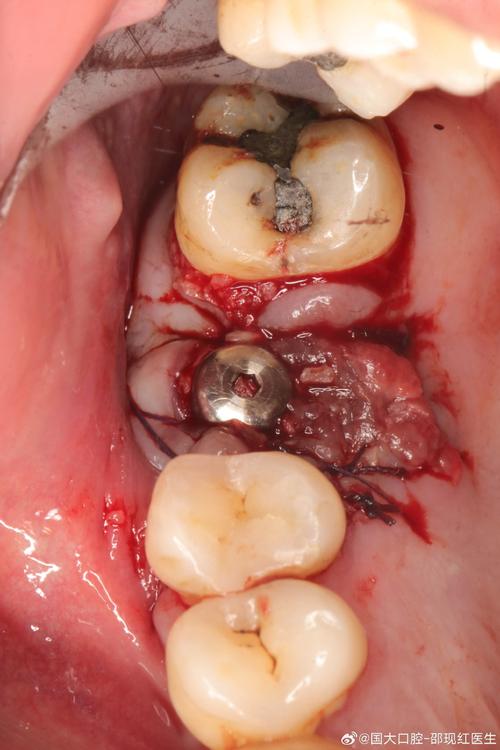

植骨手术需切开牙龈、剥离黏骨膜、制备骨窝、植入骨粉和种植体,这些操作会对软硬组织造成机械性损伤,术后局部血管扩张、通透性增加,炎性细胞(如中性粒细胞、巨噬细胞)聚集,导致牙龈组织出现肿胀、疼痛、轻微出血,通常伴随局部皮温升高,这种反应是机体修复的必经过程,多数在术后3-5天内逐渐缓解,若护理得当,7-10天可明显消退。

植骨材料的生物相容性问题

植骨所用的骨粉、骨膜等材料若生物相容性不佳,或患者对材料成分过敏,可能引发局部免疫排斥反应,表现为牙龈持续性肿胀、充血,甚至材料暴露、排出,若骨粉颗粒过大、植入量过多,或与骨床结合不紧密,可能形成死腔,积液后引发异物反应性炎症。